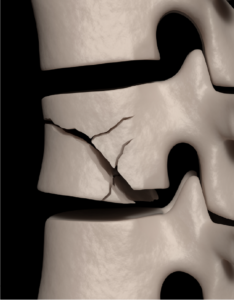

Vertebral Compression Fractures

Back pain is an indication of stress fractures known as vertebral compression fractures. Vertebral compression fractures occur when the normal vertebral body…

Spondylolysis

Spondylolysis is a stress fracture of vertebra that may progress into spondylolisthesis, a condition of displacement of vertebrae from the spinal column.